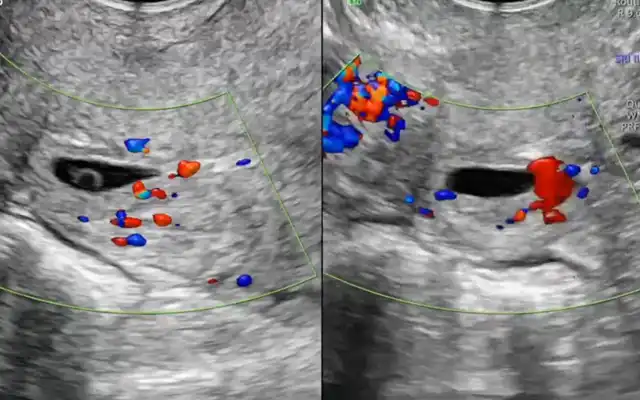

Spontaneous Heterotopic pregnancy with Twin Live Intrauterine Gestation and Ovarian Ectopic: A Case Report

Spontaneous Heterotopic pregnancy with Twin Live Intrauterine Gestation and Ovarian Ectopic: A Case Report2025-12-18T13:17:37+00:00